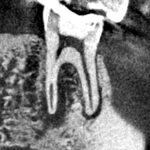

6カ月後の経過観察時のCT画像です。下顎第二小臼歯と第一大臼歯の根の先にあった膿の影が消え、歯槽骨が再生しています。